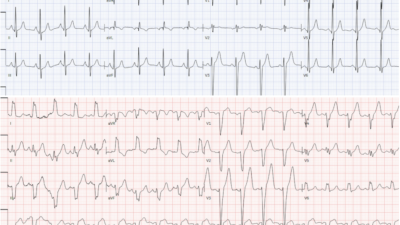

Acute right heart strain was suspected on ECG and bedside echo.

- Acute pulmonary embolism was confirmed on CT angiogram:

- CT angiogram confirmed the diagnosis of acute PE.